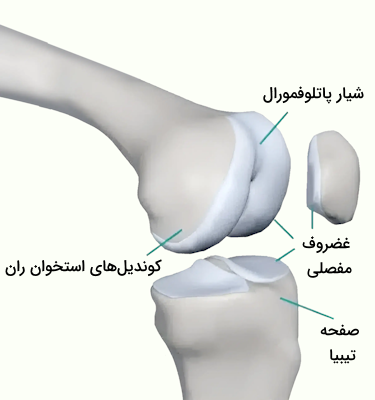

در انتهای استخوان ران دو سطح مفصلی گرد وجود دارند که به آن «کوندیل» (Condyle) میگوییم. کوندیلهای استخوان ران در مقابل دو سطح مفصلی روی استخوان درشتنی قرار دارند که به نسبت صاف به نظر میرسد اما در حقیقت اندکی مقعر است. رباطهای صلیبی که یکی از انواع رباطهای مفصل زانو هستند از فاصله بین دو کوندیل میگذرند و به دو برجستگی کوچک متصل میشوند که بین کوندیلهای استخوان ران و استخوان درشت نی قرار دارند.

کشکک زانو در بخش جلویی استخوان ران قرار دارد و به کمک تاندون زانو یا «تاندون کشککی» (Patellar Tendon) که با عنوان رباط کشکی نیز شناخته میشود، به درشتنی متصل میشود. سطح داخلی کشکک زانو گُوِهای شکل است و با غضروف مفصلی پوشیده شده است؛ این سطح در حین خم یا صاف شدن زانو در امتداد شیاری که روی استخوان ران وجود دارد، میلغزد. استخوان کشکک زانو مانع از لغزش جانبی تاندون میشود، همچنین میتواند اثر استخوان ران به عنوان یک اهرم را افزایش دهد که نتیجه آن تقویت انتقال نیرو است.

مفصل تیبیوفمورال

«مفصل تیبیوفمورال» (Tibiofemoral Joint) مفصلی است که بین کوندیلهای داخلی و خارجی انتهای دیستال فمور (استخوان ران) و «صفحههای تیبیا» (Tibial Plateaus) قرار دارد. سطح هر دو استخوان شرکت کننده در این ساختار با لایهای ضخیم از غضروف هیالین پوشیده شده است.

کوندیلهای داخلی و خارجی دو برآمدگی استخوانی با سطحی محدب و صاف هستند که در انتهای دیستال فمور قرار دارند. این دو کوندیل در بخش عقبی توسط شیاری عمیق به نام «حفره بینکوندیلی» (Intercondylar Fossa) از یکدیگر جدا شدهاند «کوندیل داخلی» (Medial Condyle) بزرگتر، باریکتر و برجستهتر از کوندیل خارجی است. تفاوت اندازه بین این دو کوندیل باعث ایجاد زاویهای بین فمور و درشت نی یا «تیبیا» (Tibia) میشود. سطوح خارجی کوندیلها را که ظاهری زبر دارند، با عناوین «اپیکوندیل خارجی» و «اپیکوندیل داخلی» میشناسیم.

صفحههای تیبیا سطوح فوقانی کوندیلها هستند که یکی از ویژگیهای خاص آنها این است که کمی مقعر هستند. این دو صفحه در انتهای پرگزیمال تیبیا یا درشتنی قرار دارند و توسط برآمدگی استخوانی از یکدیگر جدا میشوند که آن را با نام «برآمدگی بینکوندیلی» (Intercondylar Eminence) میشناسیم. سطوح داخلی مفصل درشتنی ظاهی بیضیشکل دارد، اما سطح مفصل خارجی ظاهری کرویتر دارد.

مفصل پاتلوفمورال

«مفصل پاتلوفمورال» (Patellofemoral Joint) یک مفصل مسطح است که به دلیل اتصال سطح کشککی استخوان ران به سطح پشتی استخوان کشکک ایجاد شده است. سطح کشککی استخوان ران در اصل یک شیار در قسمت جلویی انتهای استخوان ران است که به سمت پشت ادامه مییابد تا به داخل حفره موجود میان کوندیلها برسد. «کشکک» (patella) استخوانی مثلثیشکل است که بخشهای تحتانی و راسی آن ظاهری متفاوت دارند.

- بخش تحتانی: خمیده

- بخش راسی: تیز

مفصل استخوان کشکک دارای دو سطح درونی و بیرونی است هر دو سطح ظاهری مقعر دارند و با لایهای ضخیم از غضروف شیشهای نیز پوشیده شدهاند. سطح بیرونی و درونی توسط یک تیغه عمودی از یکدیگر جدا شدهاند.

استخوان کشکک در اصل از دسته استخوانهای کنجدی یا «استخوانهای سزاموئید» (Sesamoid Bones) است. استخوانهای کنجدی، استخوانهایی کوچک هستند که در نزدیکی سطوح مفصل در میان یک ماهیچه یا تاندون قرار دارند. با توجه به این ویژگی باید بگوییم که استخوان کشکک درون تاندون ماهیچه چهارسر ران جا گرفته است و محکم در جای خود نگه داشته شده است. در بخش انتهایی یا دیستال کشکک، شاهد گسترش یافتگی تاندون چهارسر راه هستیم که در نهایت نوار مرکزی محکمی به نام «رباط کشککی» را میسازد.